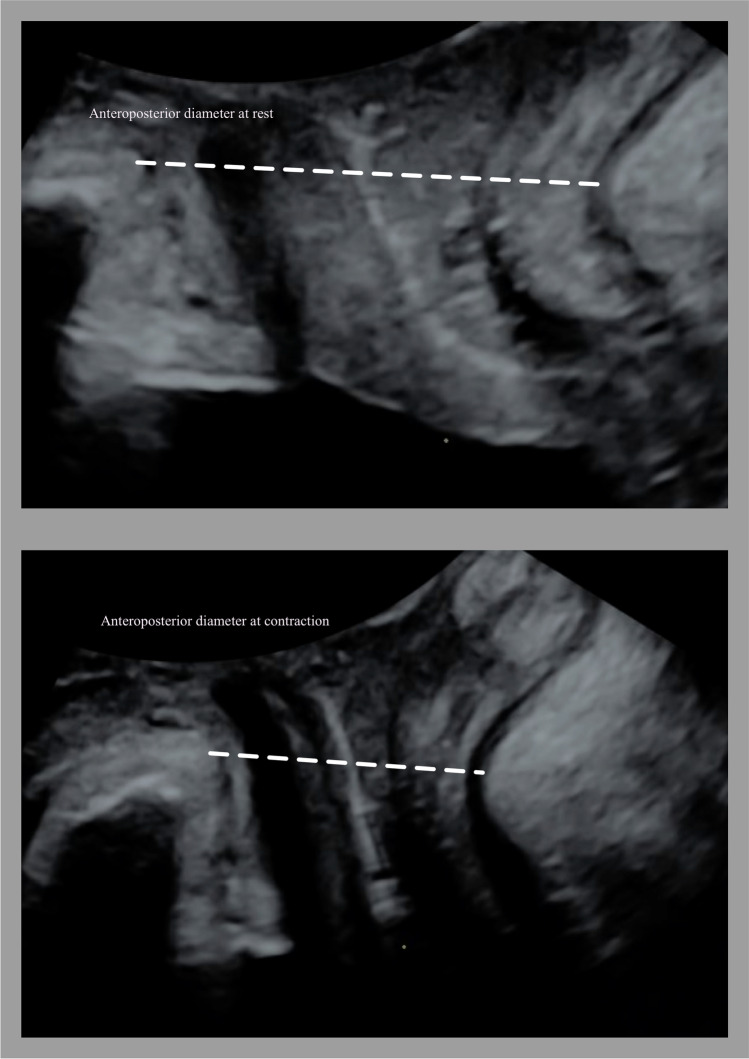

Fig. 3.

Assessment of pelvic floor contraction by ultrasound. Measurement of the anteroposterior diameter of the levator hiatus as the distance from the symphysis pubis to the puborectalis muscle at rest (top) and contraction (bottom)

Women were assessed using transperineal ultrasound. Three volumes were captured from rest to maximum contraction and three from rest to maximum Valsalva [17] using a Voluson GE S10 or E8 equipped with a RAB 4–8 MHz curved array transducer. The acquisition angle was set at 85° and the probe placed in the midsagittal plane. The volumes were analysed off-line a minimum 6–12 months after recording with 4D view by one examiner (MØN), blinded to clinical information. The offline analysis included assessment of LAM trauma, defined as abnormal insertion of the levator muscle on one or both sides of the pubic bone in all three central slices on tomographic ultrasound at contraction (Fig. 2) [18]. Pelvic floor contraction was assessed measuring the proportional change in levator hiatal anteroposterior diameter in 2D from rest to contraction using the formula: 100 × [(measurement rest − measurement contraction)/measurement rest] (Fig. 3) [13]. Muscle contraction was categorised as absent (<1%), weak (2–14%), normal (15–29%) or strong (>30%) [13], and we dichotomised contraction into absent to weak or normal to strong.